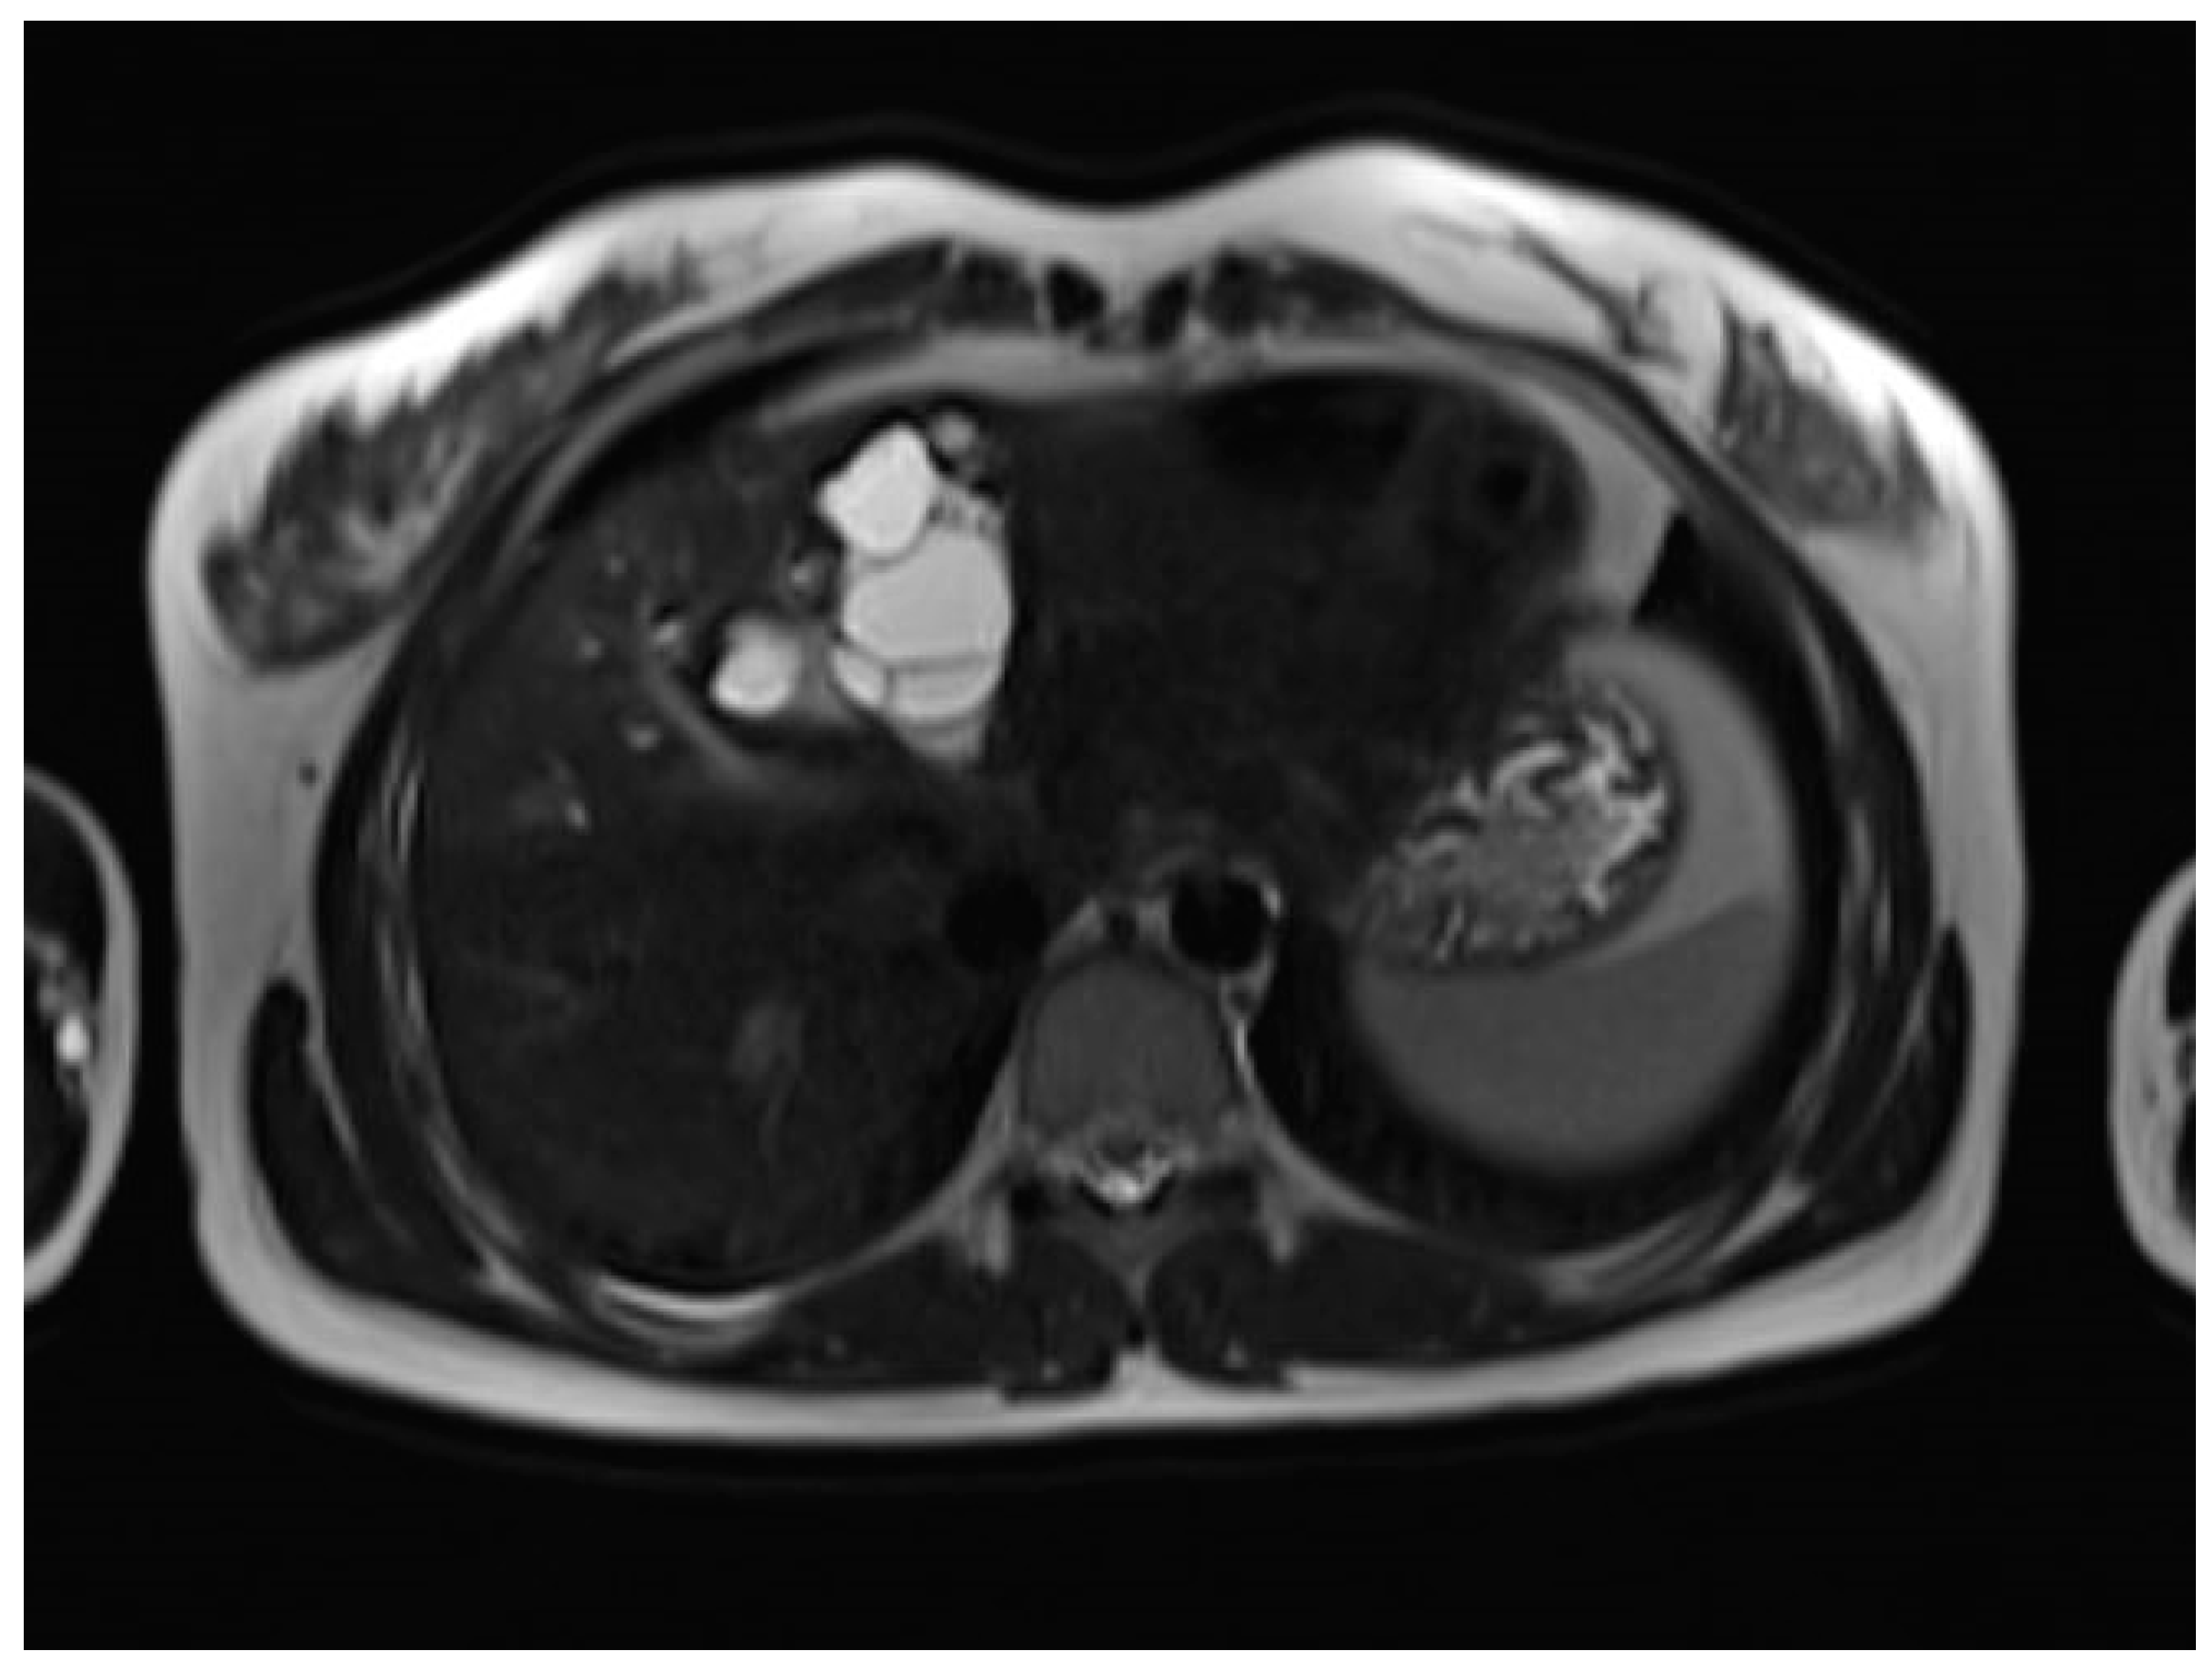

A liver MRI scan confirmed a cystic structure with multiple daughter cysts, hypointense on a T1-weighted image (T1WI), and hyperintense on a T2-weighted image (T2WI), with no solid components, no signs of membrane rupture, and a maximum diameter of 10 cm (craniocaudal) (Figure 1). Additionally, elevated signals on T2WI in the surrounding liver tissue were found. The T1 sequences did not reveal any contrast uptake after 5 (Figure 2), 10, or 20 (Figure 3) minutes post-injection. Furthermore, DWI/ADC mapping indicated a hydatid cyst. The DWI sequences included a trace DWI (Figure 4), an ADC map (Figure 5), and both at b800. Radiomics and AI tools were not involved. The trace DWI showed an area of hypointensity in the region of the cyst that was surrounded by a hypointense layer, depicting the cystic wall. The ADC map revealed hyperintensity within the area, in concordance with a typical depiction of cysts on an MRI scan.

Figure 1.

First MRI scan: Axial T2W MRI scan revealing hyperintense areas in liver segment IV, suspicious daughter cysts, and clearly visible septation.

MR imaging clearly visualizes pericyst, matrix, and daughter cysts. The pericyst appears as a hypointense rim on both T1WI and T2WI due to its fibrous structure and the presence of calcifications. This is a specific feature of hydatid cysts, called the rim sign, mostly better visualized on T2WI [5]. The matrix represents hydatid-fluid-containing membranes of broken daughter vesicles, scolices, and hydatid sand [7]. The hydatid matrix appears hypointense on T1WI and significantly hyperintense on T2WI. However, the limitations of MRI scans are especially observed in stages CE4–CE5, as bigger calcifications are better observed on a CT scan. When daughter cysts are present, they are typically more hypointense than the matrix on T2WI, as observed in our case report [17] (Figure 1). If the membrane is separated, it can shift with movement, resembling a water lily floating on the surface of a pond, previously described as water-lily sign, which was seen in our case report as well [18] (Figure 8).